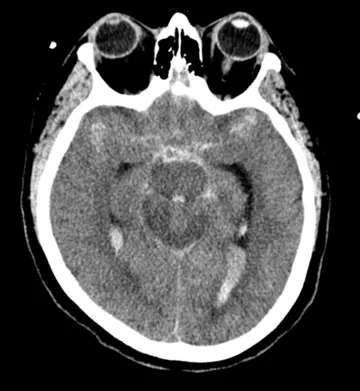

A CT scan is performed which almost always shows the bleeding (fig. 2). If the blood load is very low then rarely it does not show up and a lumbar pucnture is performed to detect red blood cells in the CSF.

Figure 2: CT scan of a ruptured aneurysm showing blood around the brain.